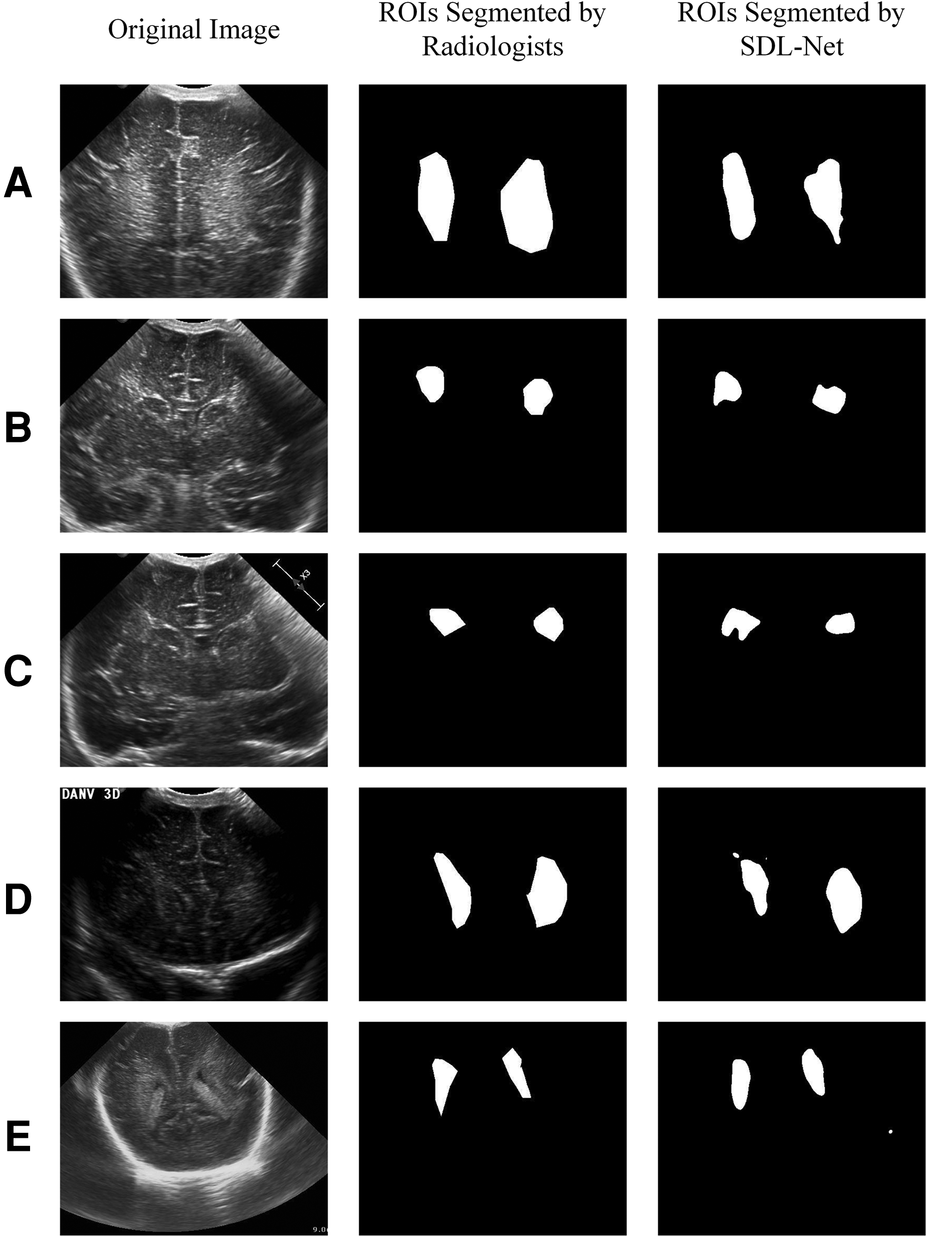

We used training cohort to train the parameters in SDL-Net, and then used testing cohort to evaluate the segmented results. As shown in Figure 7, we can see that the segmented result by SDL-Net is slightly different from the golden standard ROIs segmented by radiologists. The result is listed in Table 4. It can be observed that our method on testing cohort has an overall Dice of 0.73, an accuracy of 0.80, and an IoU of 0.72.

Figure 7

White matter ROIs segmented by SDL-Net.

Then we used our segmented result in ultrasound radiomics diagnostic system. The result is listed in Table 3. As shown, AUC of SVM based C-SVC reached 0.819 in the testing cohort. The ROC curves of SVM based C-SVC in testing cohort is shown in Figure 8.